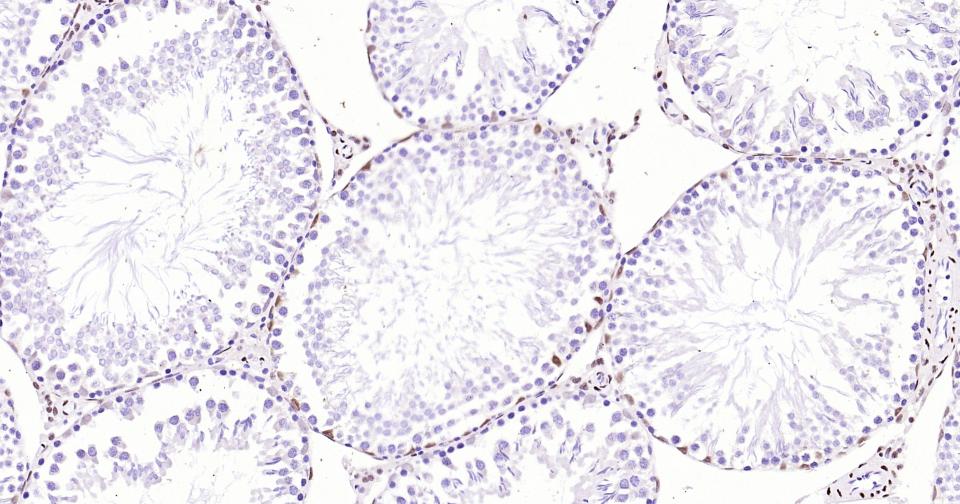

Paraformaldehyde-fixed, paraffin embedded Mouse Testicles; Antigen retrieval by boiling in sodium citrate buffer (pH6.0) for 15 min; Antibody incubation with Androgen receptor Monoclonal Antibody, Unconjugated(bsm-61204R) at 1:200 overnight at 4°C, followed by conjugation to the SP Kit (Rabbit, SP-0023)and DAB (C-0010) staining.